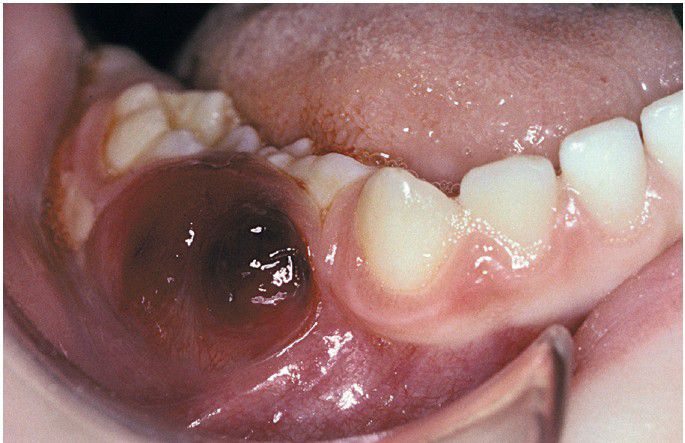

Langerhans Cell Histiocytosis

The lesion has broken out of bone and produced this soft tissue mass.